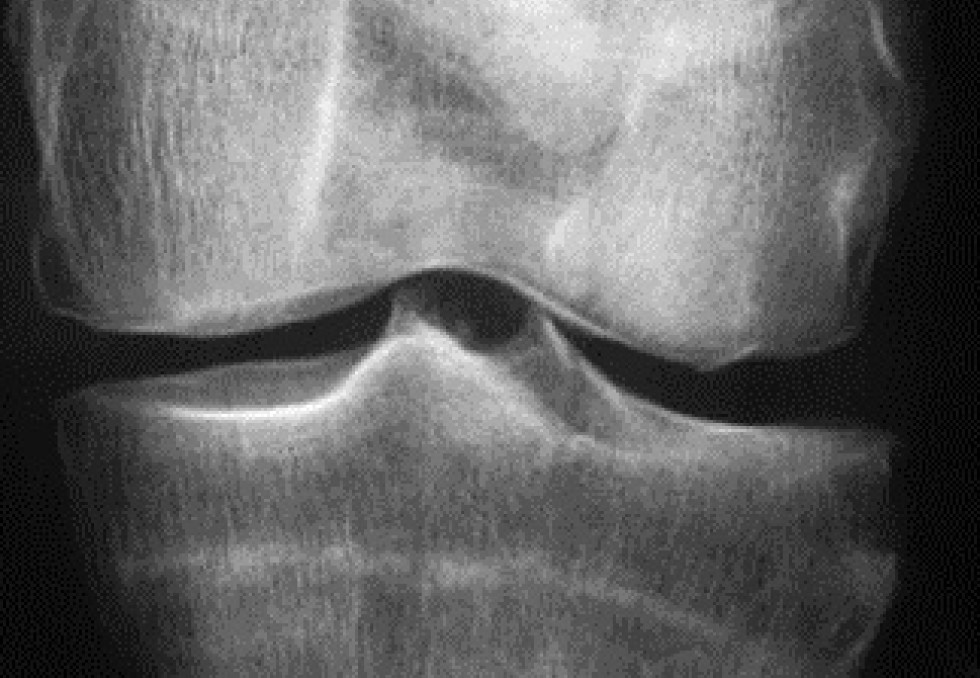

Première cause d’incapacité fonctionnelle après 40 ans, l’arthrose affecterait plus de 10 millions de Français selon l’Aflar, l’Association française de lutte antirhumatismale. Au plan thérapeutique, l’arsenal dont disposent les médecins, généralistes et rhumatologues, a peu évolué au cours de ces dernières années.

Surtout, le déremboursement récent des anti-arthrosiques symptomatiques d’action lente (AASAL) a porté un rude coup à la prise en charge médicale de l’arthrose, laissant craindre une plus forte iatrogénie liée à d’autres classes de médicaments, notamment les AINS dont la prescription augmente au fur et à mesure que reculent les prescriptions des AASAL depuis leur déremboursement. Toutefois, de nouvelles perspectives se présentent avec un candidat-médicament découvert par une biotech, Galapagos, associée pour le développement de ce candidat-médicament au laboratoire Servier. Ce candidat-médicament, GLPG1972, est le premier d’une possible nouvelle classe thérapeutique ciblant une enzyme responsable de la dégradation du cartilage, appelée ADAMTS-5. Au cours de la phase 1 de développement de ce médicament, il a été démontré sur des volontaires sains que GLPG1972 réduisait de plus de 50%, en moins de deux semaines, le néoépitope ARGS, marqueur important de la dégradation du cartilage. Un essai de phase 2 est actuellement en cours de préparation. Dans le cadre de ce partenariat signé entre Galapagos et Servier, le laboratoire français acquiert les droits de commercialisation de GLPG1972 dans le monde entier, hors Etats-Unis où Galapagos conserve les droits exclusifs de commercialisation.